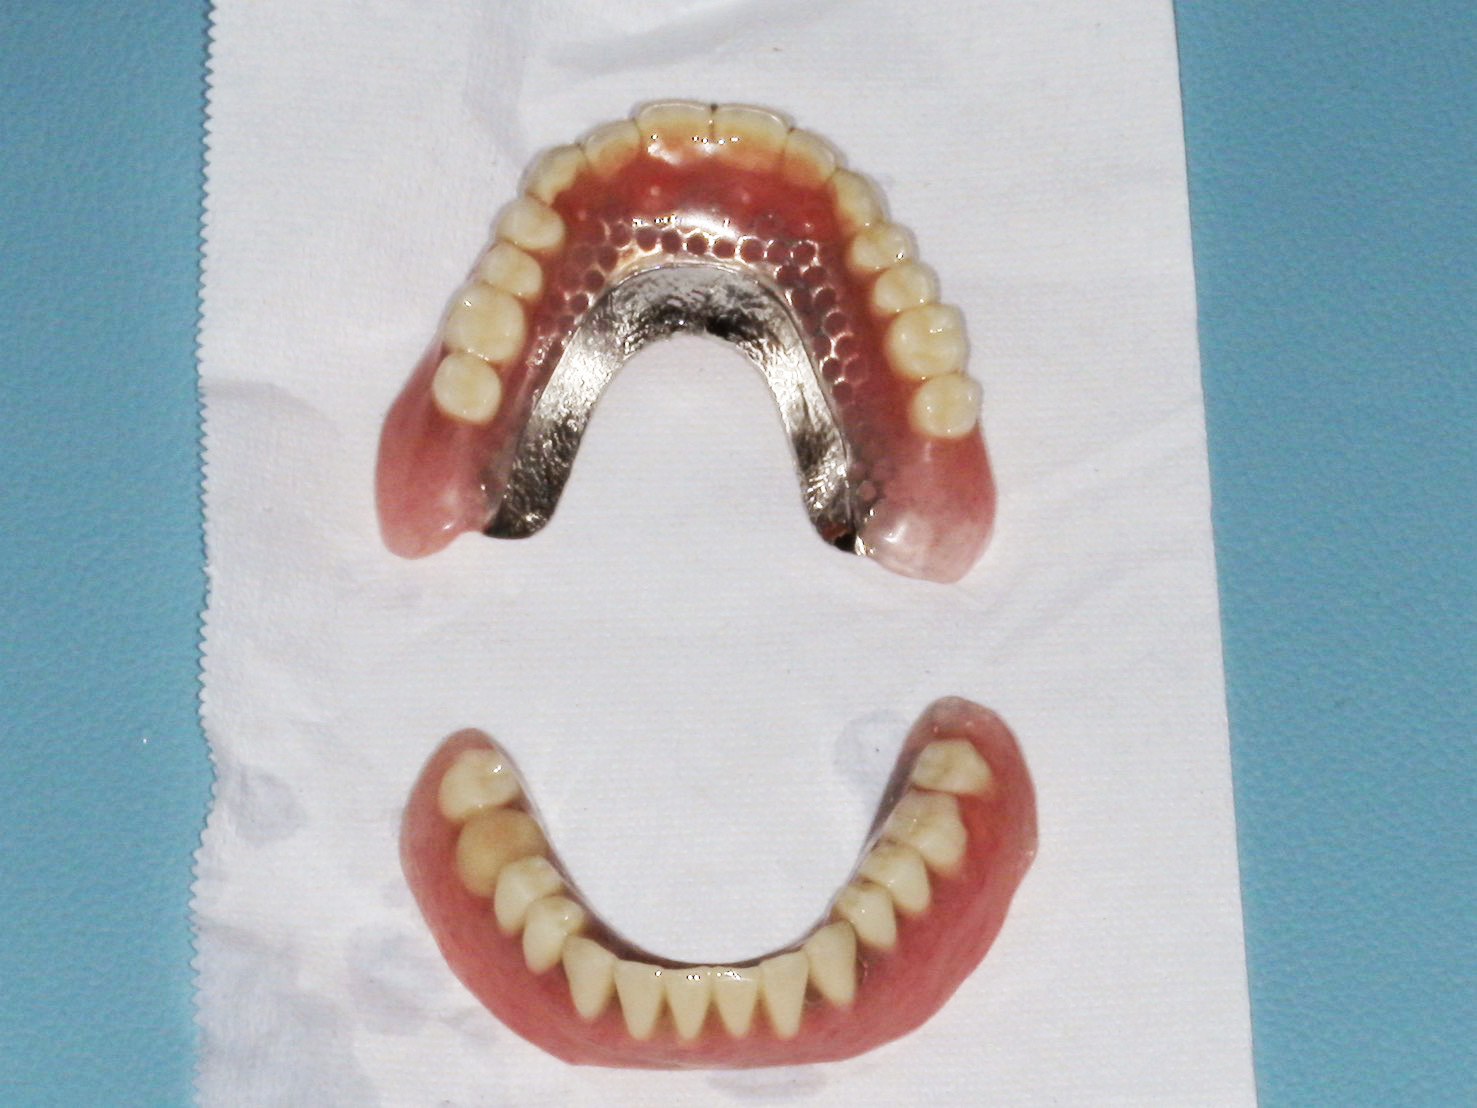

完成した義歯が以下です。

義歯の穴が空いてる部分にマグネットを埋め込んでます。今回は金属床義歯で作製してます。